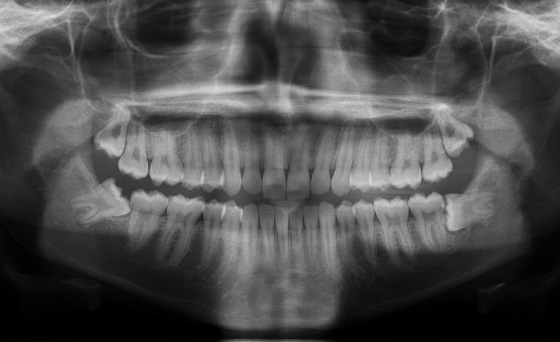

The most common X-Ray required is an OPG, which will show all the wisdom teeth, it will reveal signs of infection or other pathology, it will highlight the relation of the wisdom tooth to the adjacent molars and will show the proximity of the roots of the wisdom tooth to the inferior dental nerve.